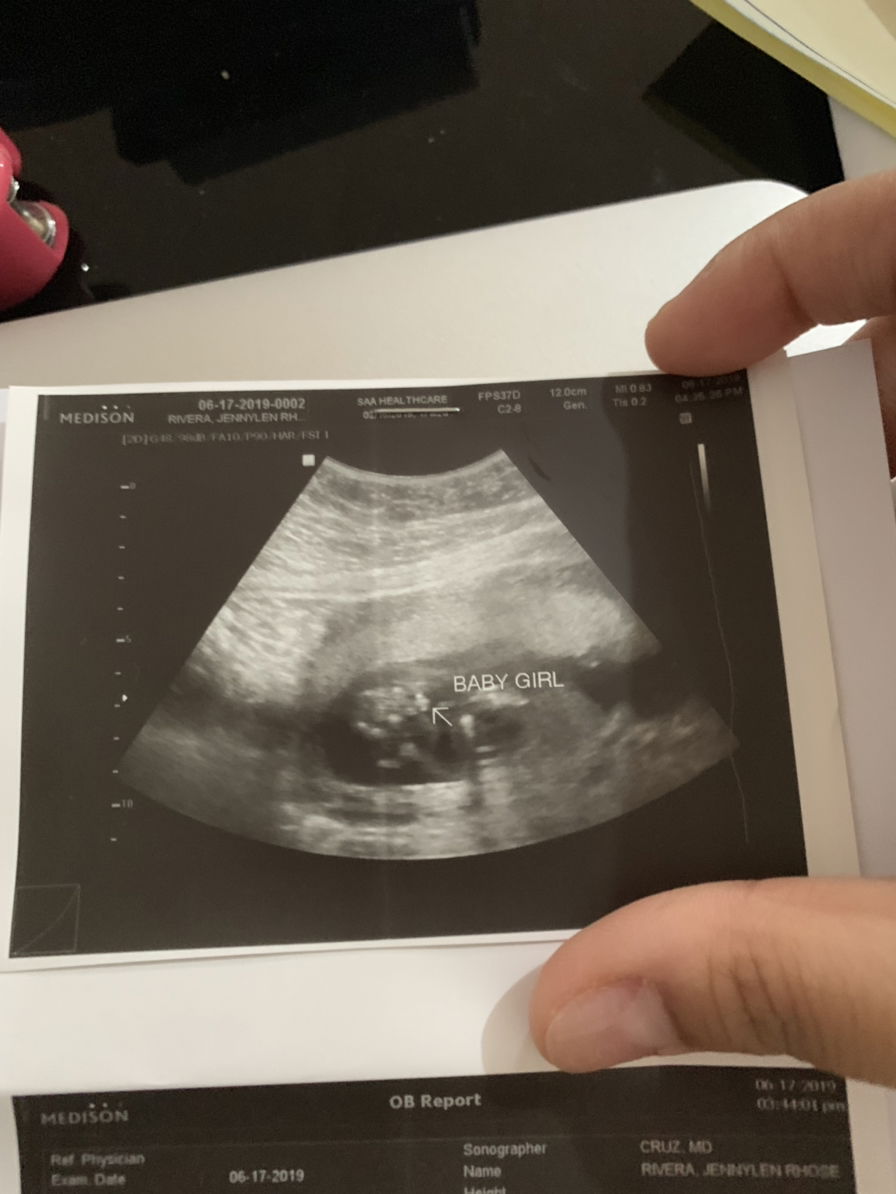

17weeks ultrasound

Question pwede ba mamali ang ultrasound? I had my gender check ultrasound on my 17weeks actually naka twice kami kasi una di tlga makita then the other day bumalik ako baka raw makita na on my first salang wala di pa din makita then pinatayo ako at pinaglakad lakad tapos inom cold water para gumalaw then salang na ulit medyo hirap makita, then later on my ob says it's a girl raw pero my husband still doubt about the gender baka di pa sure un nakita ng doctor. Haay kasi super excited lang ako malaman gender. Anyone may scenario ba kayo namali sa ultrasound?